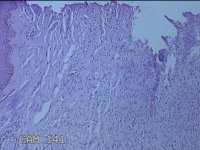

左侧眼眉部结节

性别

男

年龄

51岁

临床诊断

皮下结节

一般病史

发现左侧眼眉部结节2年余。

标本名称

大体所见

灰白暗红色结节0.8x0.7x0.2cm一个,表面糜烂,切开结节呈实性,切面灰白暗红色,质软。

图2